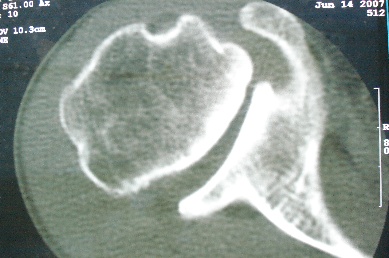

右上肢活动不便多年,最近加重。右肱骨肿瘤,请会诊!

骨软骨瘤恶变可能性大

右肱骨近断骨软骨瘤伴临近关节退变.有无恶变建议进一步检查.

右肱骨近断骨软骨瘤伴临近关节退变。

病变边缘轮廓清晰无骨质破坏,邻近软组织不肿胀,不支持肿瘤恶变。